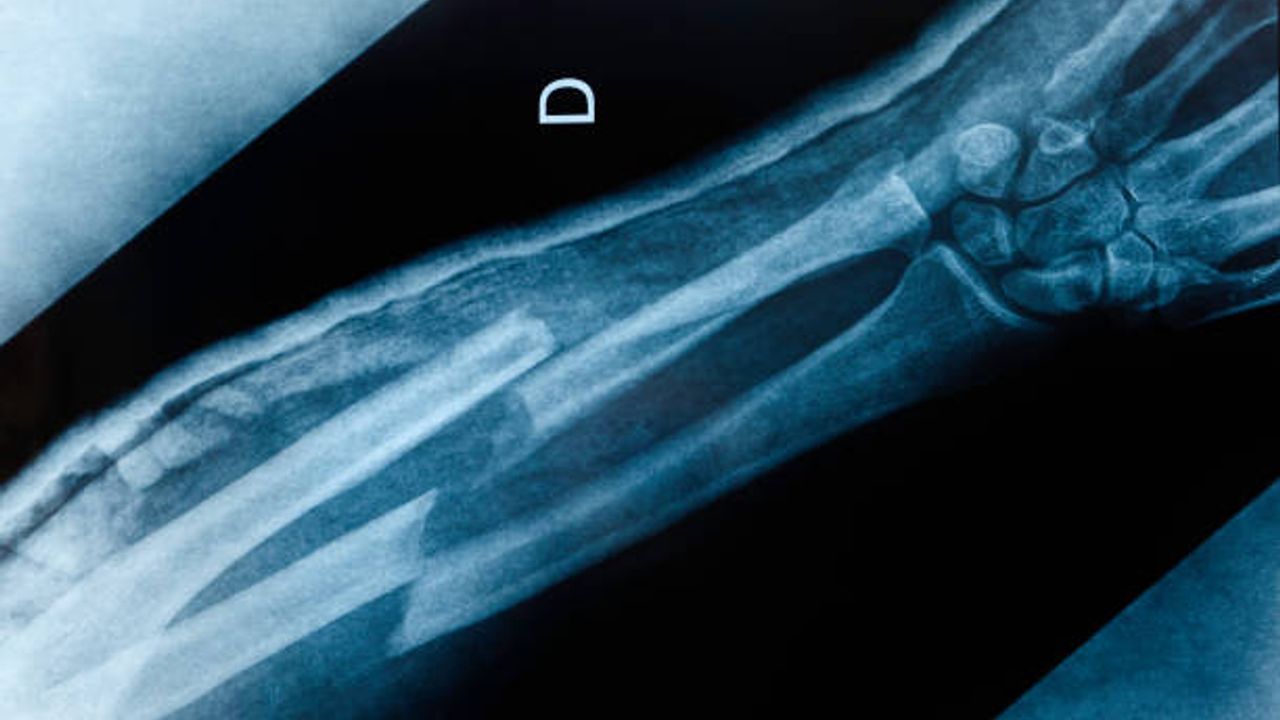

Çin'de bilim adamları, kırık kemik parçalarını yenileyen buluş niteliğinde yeni bir keşif gerçekleştirdi. Yapılan yeni çalışmayla ekipçe geliştirilen " Bone-02" isimli buluş, genel olarak haftalarca süren istirahat ve titanyum levha takılmasını gerektiren iskelet travmalarını tedavi etmeyi amaçlıyor.

Kemik yapıştırıcı yöntemi bir enjeksiyon şeklinde uygulanıyor öte yandan kemik parçalarını sadece 3 dakika içerisinde birbirine bağlıyor.

"Bone-02 " öte yandan kemik onarıcı vücudumuz tarafından doğal olarak emiliyor, böylelikle implantı çıkarmak için yeni bir ameliyat süreci tamamen kalkıyor.

İlk deneyler, kemik yapıştırıcısı kullanıldığında metal plaka yöntemlerine göre daha az enfeksiyon oluştuğunu gösteriyor.